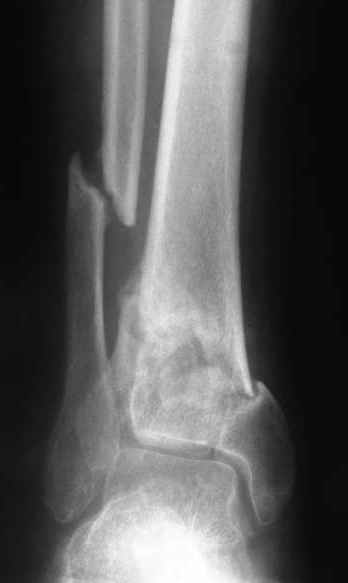

A 56 year old laborer fell off a wall approximately 5 months ago. He sustained an open pilon fracture. He was treated with debridement and external fixation. After he was treated for 4 months, the external fixator was removed.

I have attached his x-rays. I have also attached an WMV movie file of his axial CT (if you are unable to view this, I can post an MPEG file).

It seems to be a definite nonunion from the plain XRs.

The subtalar joint looks okay from what we can see on the lateral x-ray so I wouldn't want to damage it if it can be avoided. If thorough workup (WBC, ESR, CRP) shows no evidence for infection, he's a nonsmoker (or has quit) and there's no sign of infection at surgery, I would try a "moderately invasive" ORIF with debridement and autologous bone grafting. I think with a precontoured plate with locking screw capability one could get adequate fixation distally to allow immediate ROM and provide compression across the fracture.